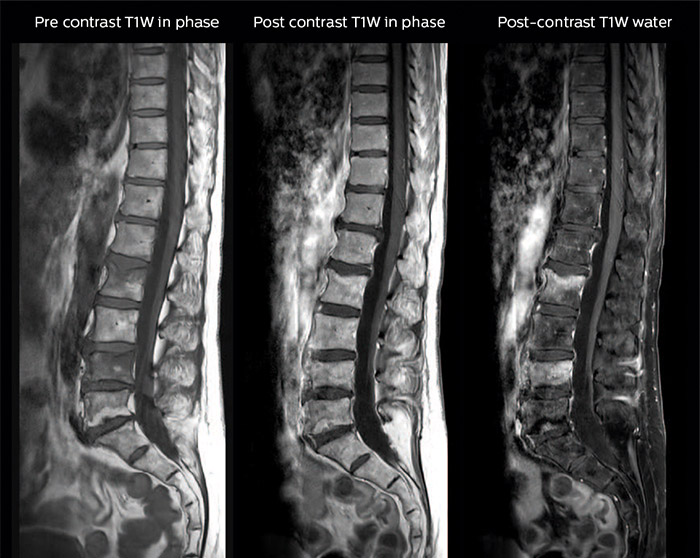

“In our spine cases, we use mDIXON TSE for patients with degenerative and inflammatory spine issues, vertebral fractures and vertebral and paravertebral tumor characterization,” says Dr. Lefebvre. “It provides, in a single acquisition, different contrasts so we can both visualize and characterize spinal, focal or diffuse spine lesions.”

“mDIXON TSE makes real a difference in cases of acute and traumatic spinal injuries, where it allows us to reduce the scan time by only using a limited number of sequences. For patients in pain, who come from the emergency unit and need surgery, for example, MRI must be very fast. With a single T2-weighted acquisition we can assess spinal cord, vertebral disc and ligament wholeness with in-phase images, as well as trabecular fracture and edematous changes with water images.”

Dr. Lefebvre cites other frequent examples of spinal diseases that benefit from the mDIXON technique. “In cases of vertebral disc herniation or degenerative discs, for example, we don’t have to choose between fat or no fat images. We can assess morphological changes in the endplate with in-phase images from T2-weighted sequences and in the water image from the same acquisition we will see inflammatory changes into endplates.”

“We can both visualize and characterize spinal, focal or diffuse spine lesions.”